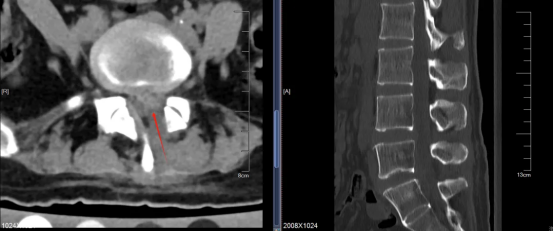

吴梅祥主任团队在宁女士腰背部做两个1厘米左右的小切口,在脊柱内镜引导下,切除了压迫神经的韧带和少量增生的腰5椎体,并摘除髓核,确保神经周围有足够空间,彻底松解了被压迫的神经。

手术效果十分显著,术后,宁女士立刻感到腰腿的放射痛和麻木感明显减轻,没有其它并发症,当日便下床运动。复查显示,原来被压得扁扁的神经根得到了充分解放,神经保护膜也恢复了饱满充盈的状态。

▲术后CT检查